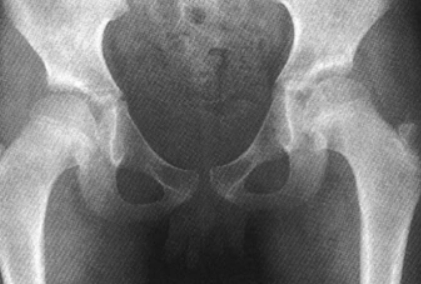

大腿与髋的影像鉴别!

1招叫你鉴别全髋与半髋,如此简单!